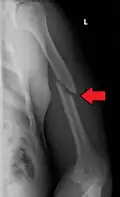

A transverse fracture of the humerus shaft -

A spiral fracture of the distal one-third of the humerus shaft -

Middle fractures are usually caused by either physical trauma or falls. Physical trauma to the humerus shaft tends to produce transverse fractures whereas falls tend to produce spiral fractures. Metastatic breast cancer may also cause fractures in the humerus shaft.[12] Long spiral fractures of the shaft that are present in children may indicate physical abuse.[5]